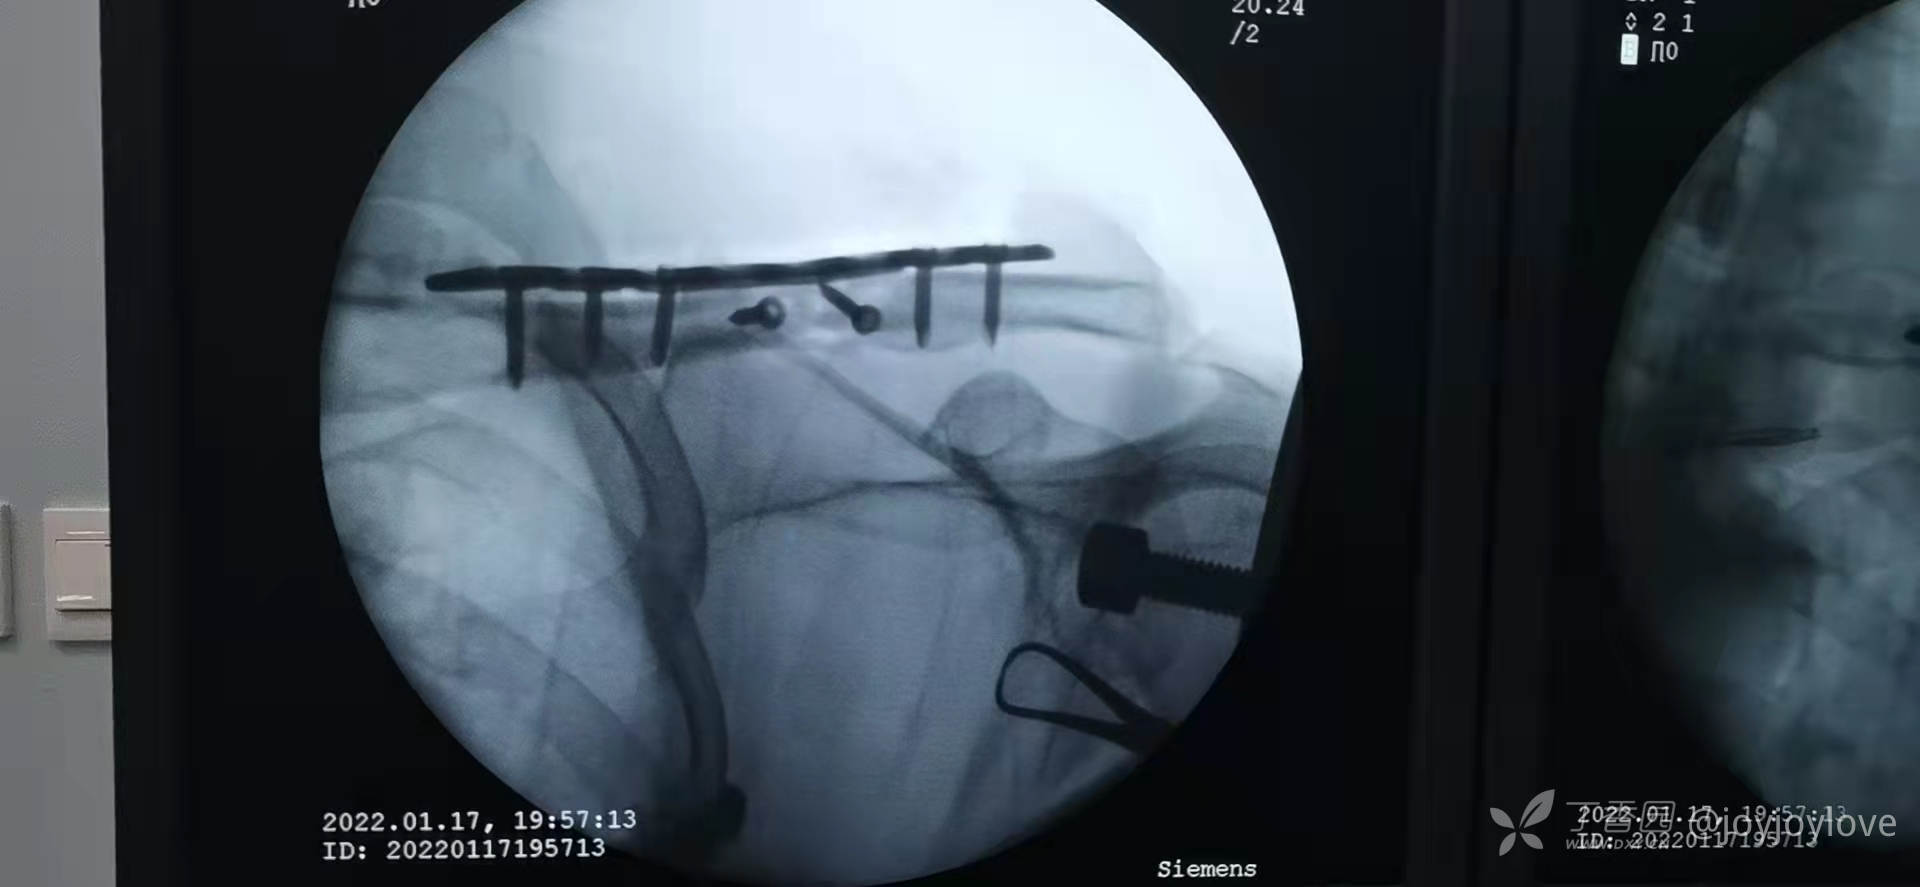

病例备忘录:2022锁骨

3.中段蝶形骨块,长斜块,3块骨折线,企图一枚拉力螺钉,结果拉力螺钉顶着皮质进,把骨折线顶开了,换成2枚拉力螺钉固定。

1.手术切口,铺单完毕后,触摸骨擦感,局部切开,暴露骨折端后再适度延长。

2.铺洞巾后,头颈部不撑起来,因为患者合并其他肋骨骨折,是全麻,不影响呼吸,所以不撑死洞巾,以免影响钻的应用

3.钻的时候满转慢推,后方垫骨膜起子,防止穿透软组织,损伤血管等软组织